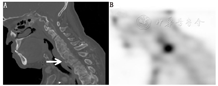

2.67Ga显像。感染病灶通过多种方式摄取67Ga。67Ga在注射后约有90%存在于血浆中,且几乎所有血浆中的67Ga最初都与转铁蛋白结合。血流量和血管壁通透性的增加会促使67Ga在感染病灶内的积聚。乳铁蛋白存在于大多数感染中,67Ga可与之结合。已有研究报道称,细菌可直接摄取67Ga。铁载体是细菌生成的一种螯合物,可与67Ga结合。铁载体-镓复合体可被转运到细菌内,并被巨噬细胞吞噬。部分67Ga可由循环血液中的白细胞进行转运。67Ga显像通常在注射后18~72 h进行。目前,67Ga显像主要用于脊柱骨髓炎的诊断(图1)[3]。

放射性核素显像可辅助MRI用于脊柱骨髓炎的诊断。虽然骨显像已被用于脊柱骨髓炎的筛查,但常出现假阴性。骨显像在探查脊柱感染伴随的软组织感染方面灵敏度低。在感染痊愈后,骨显像在一段时间内可能仍为阳性。67Ga显像的特异性比骨显像高,还可能比骨显像更快发现感染的骨病灶及伴随的软组织感染[3,17,18]。67Ga SPECT/CT显像可降低假阳性率和假阴性率,并能探查到软组织感染[3]。